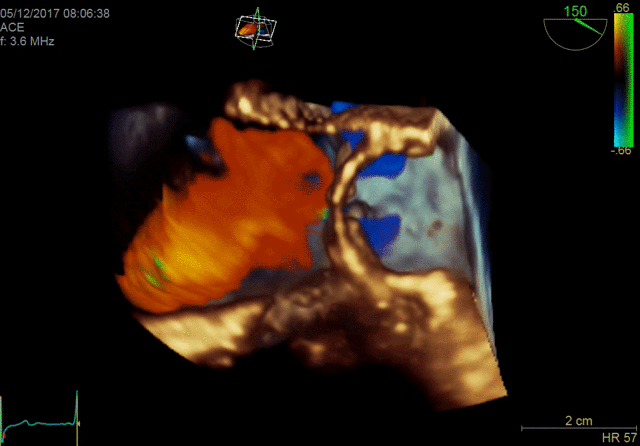

4D color imaging with the 4Vc-D probe

4D TEE color imaging with Vmax